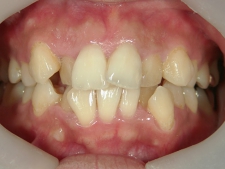

矯正歯科 治療前矯正歯科 治療前

主訴:上下の前歯の歯並びが悪いのが気になる

矯正歯科 治療前 上下左右4番 計4本を抜歯して叢生を改善しました。